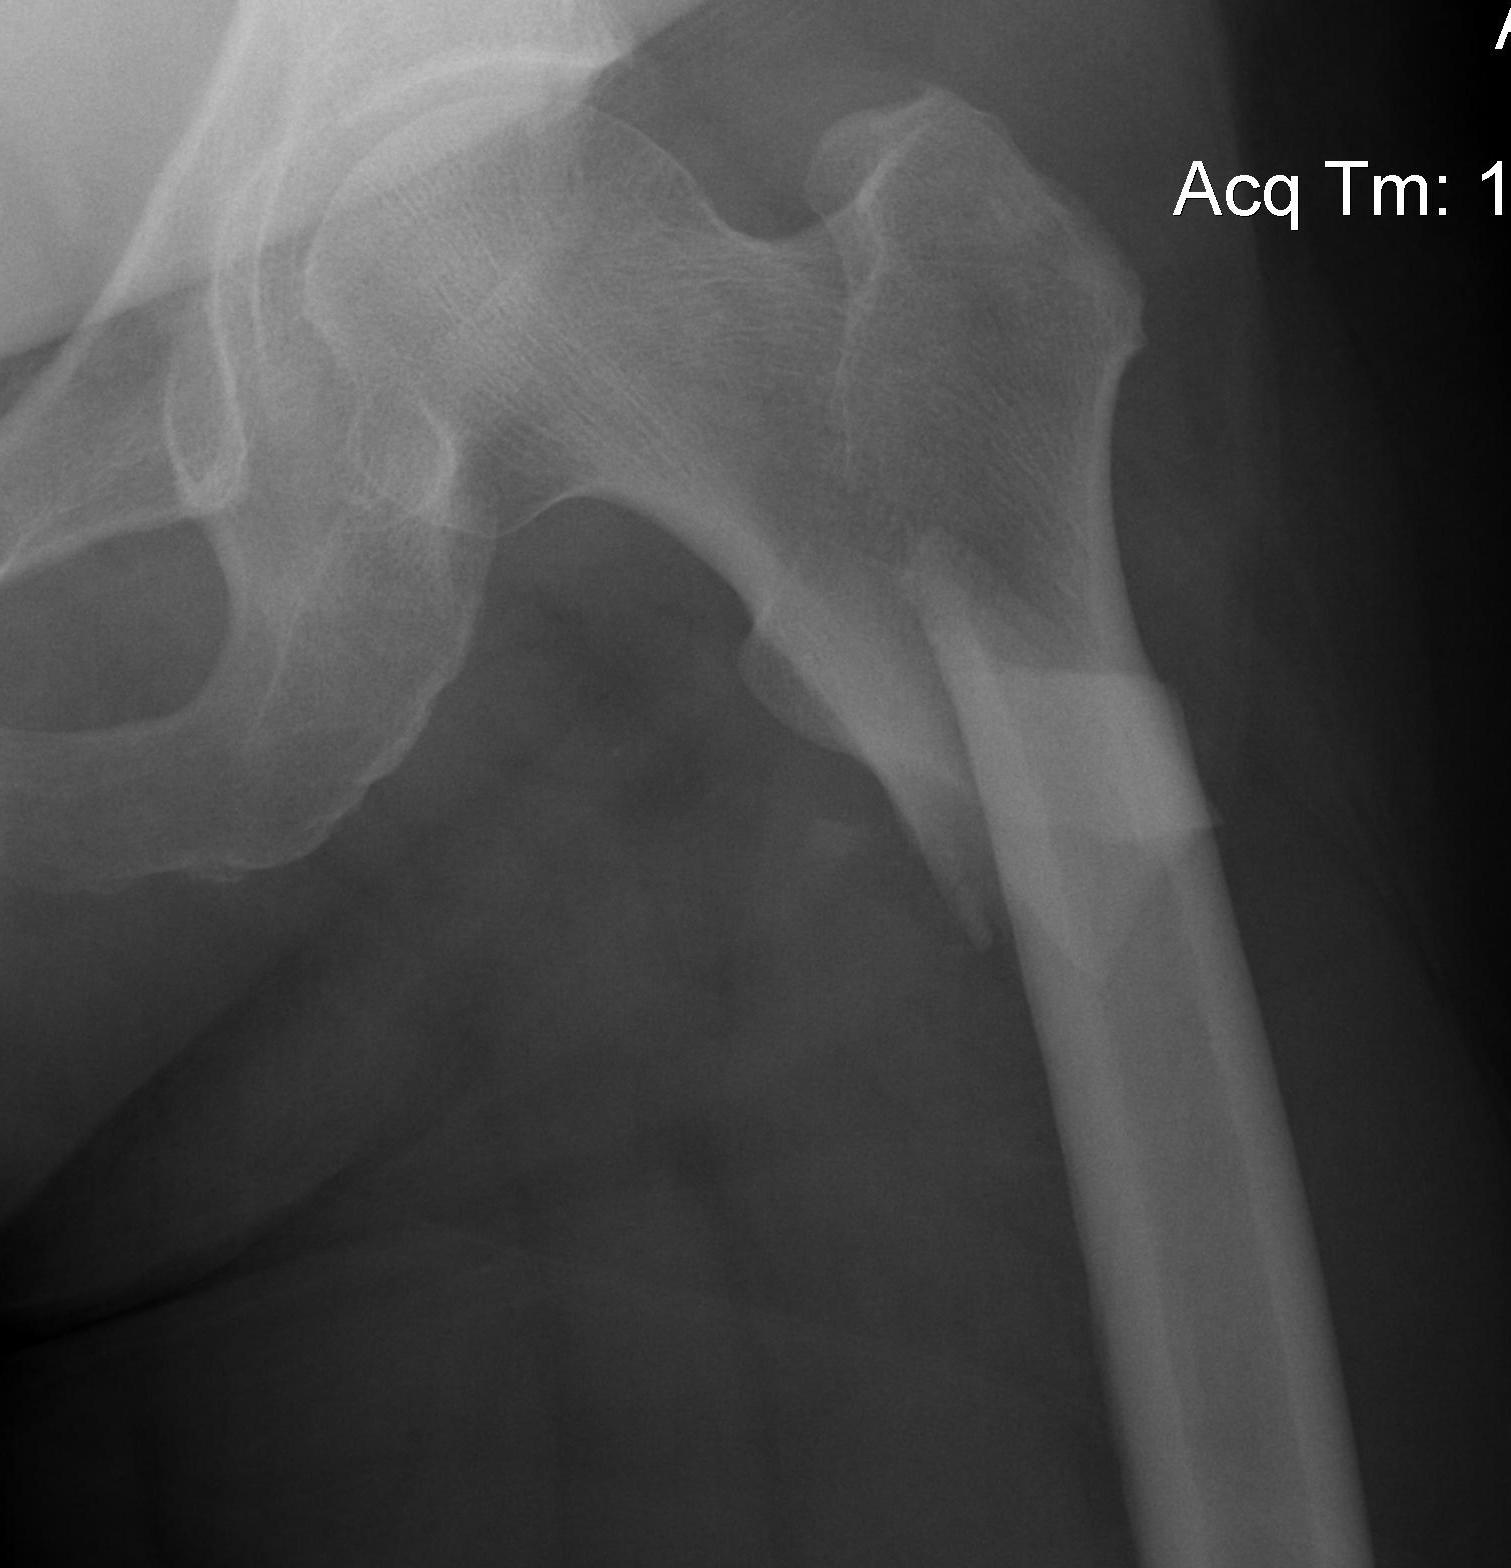

Hoffa fracture

Definition

Coronal plane fracture of distal femoral condyle

- intra-articular

- often only attachment is posterior capsule

Xray

Coronal plane fracture of distal femoral condyle

- intra-articular

- often only attachment is posterior capsule